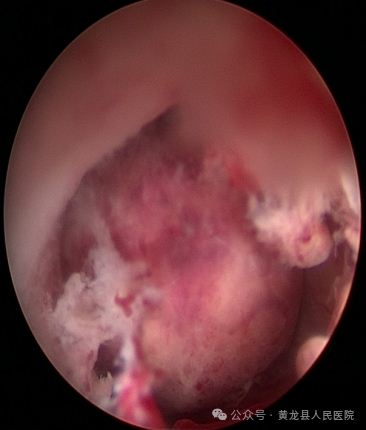

经宫腔镜子宫黏膜下肌瘤切除术(冷刀刨削)。

患者女,50岁,因不规则阴道出血11天来我院妇科就诊,彩超提示子宫后壁可见2.4cm×1.5cm低回声,考虑黏膜下肌瘤。经过严密术前评估,征求患者及家属意见后,决定实施经宫腔镜子宫黏膜下肌瘤切除术(冷刀刨削)。手术在硬腰联合麻醉下进行,宫腔镜直视肌瘤位置,见瘤体根蒂位于子宫后壁大小约3.5×2.5cm。张海红副主任医师用冷刀刨削缩小肌瘤体积,将子宫肌瘤全部取出,手术顺利,术后患者安返病房。由于宫腔镜手术没有体表手术伤口,术后6小时即可下床活动,并进食,术后2天顺利出院。术后病理检查:子宫黏膜下平滑肌瘤,与术前诊断一致。

术前宫腔术后宫腔